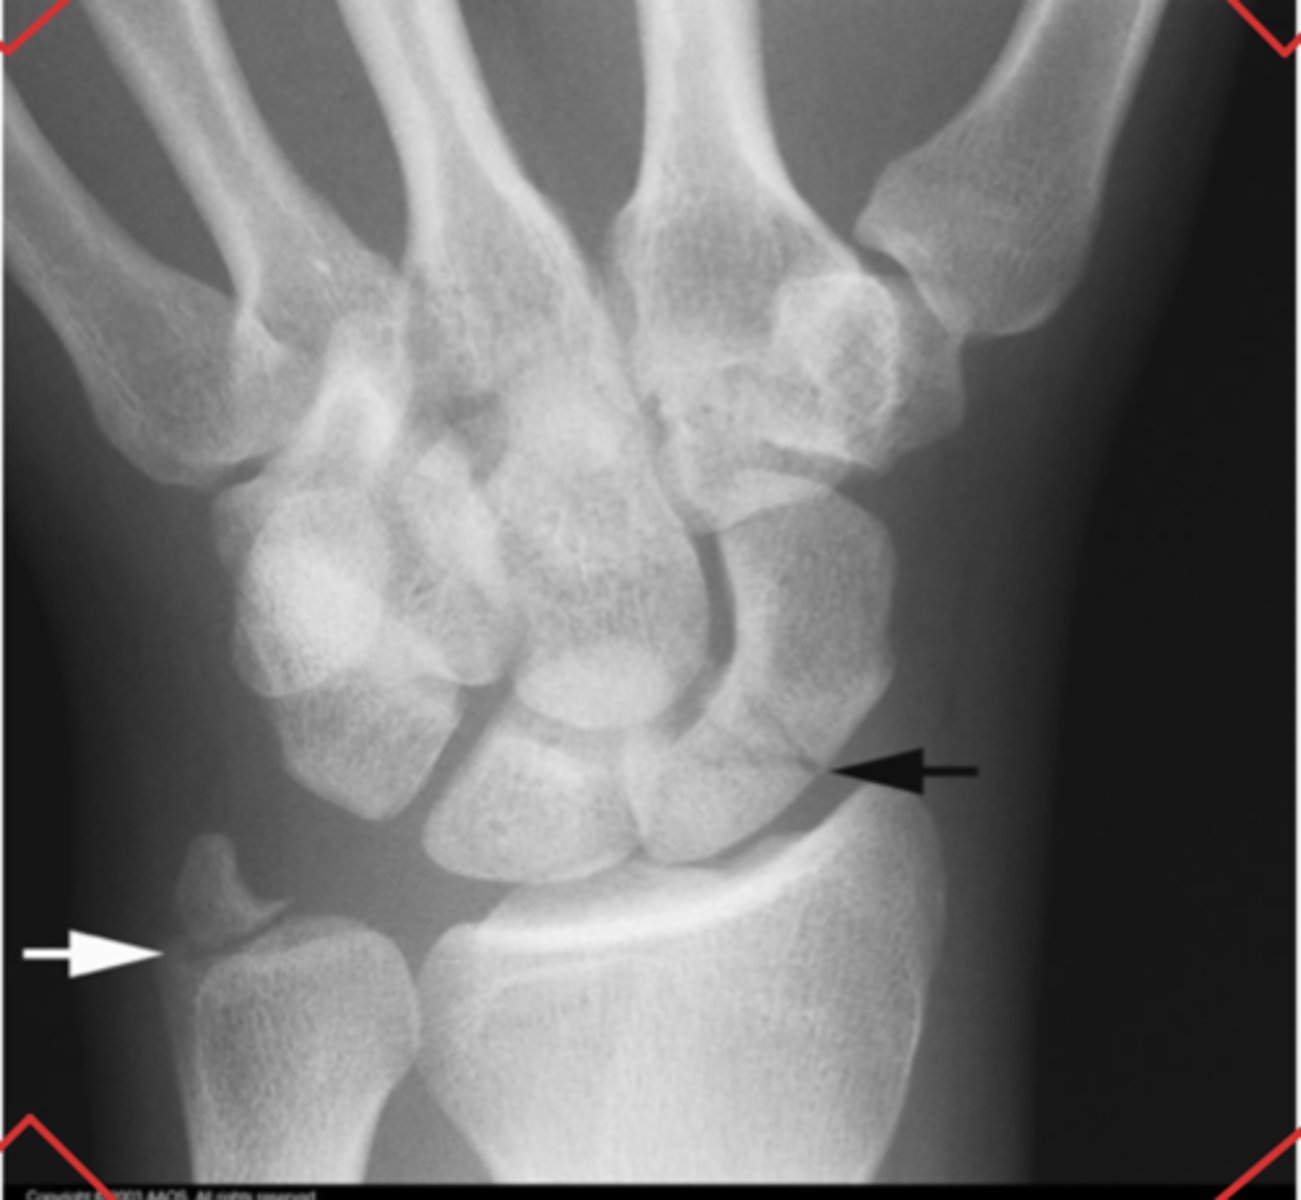

Scaphoid fracture and minor ulnar fracture

What is the issue?

Scaphoid fracture

Capitate fracture